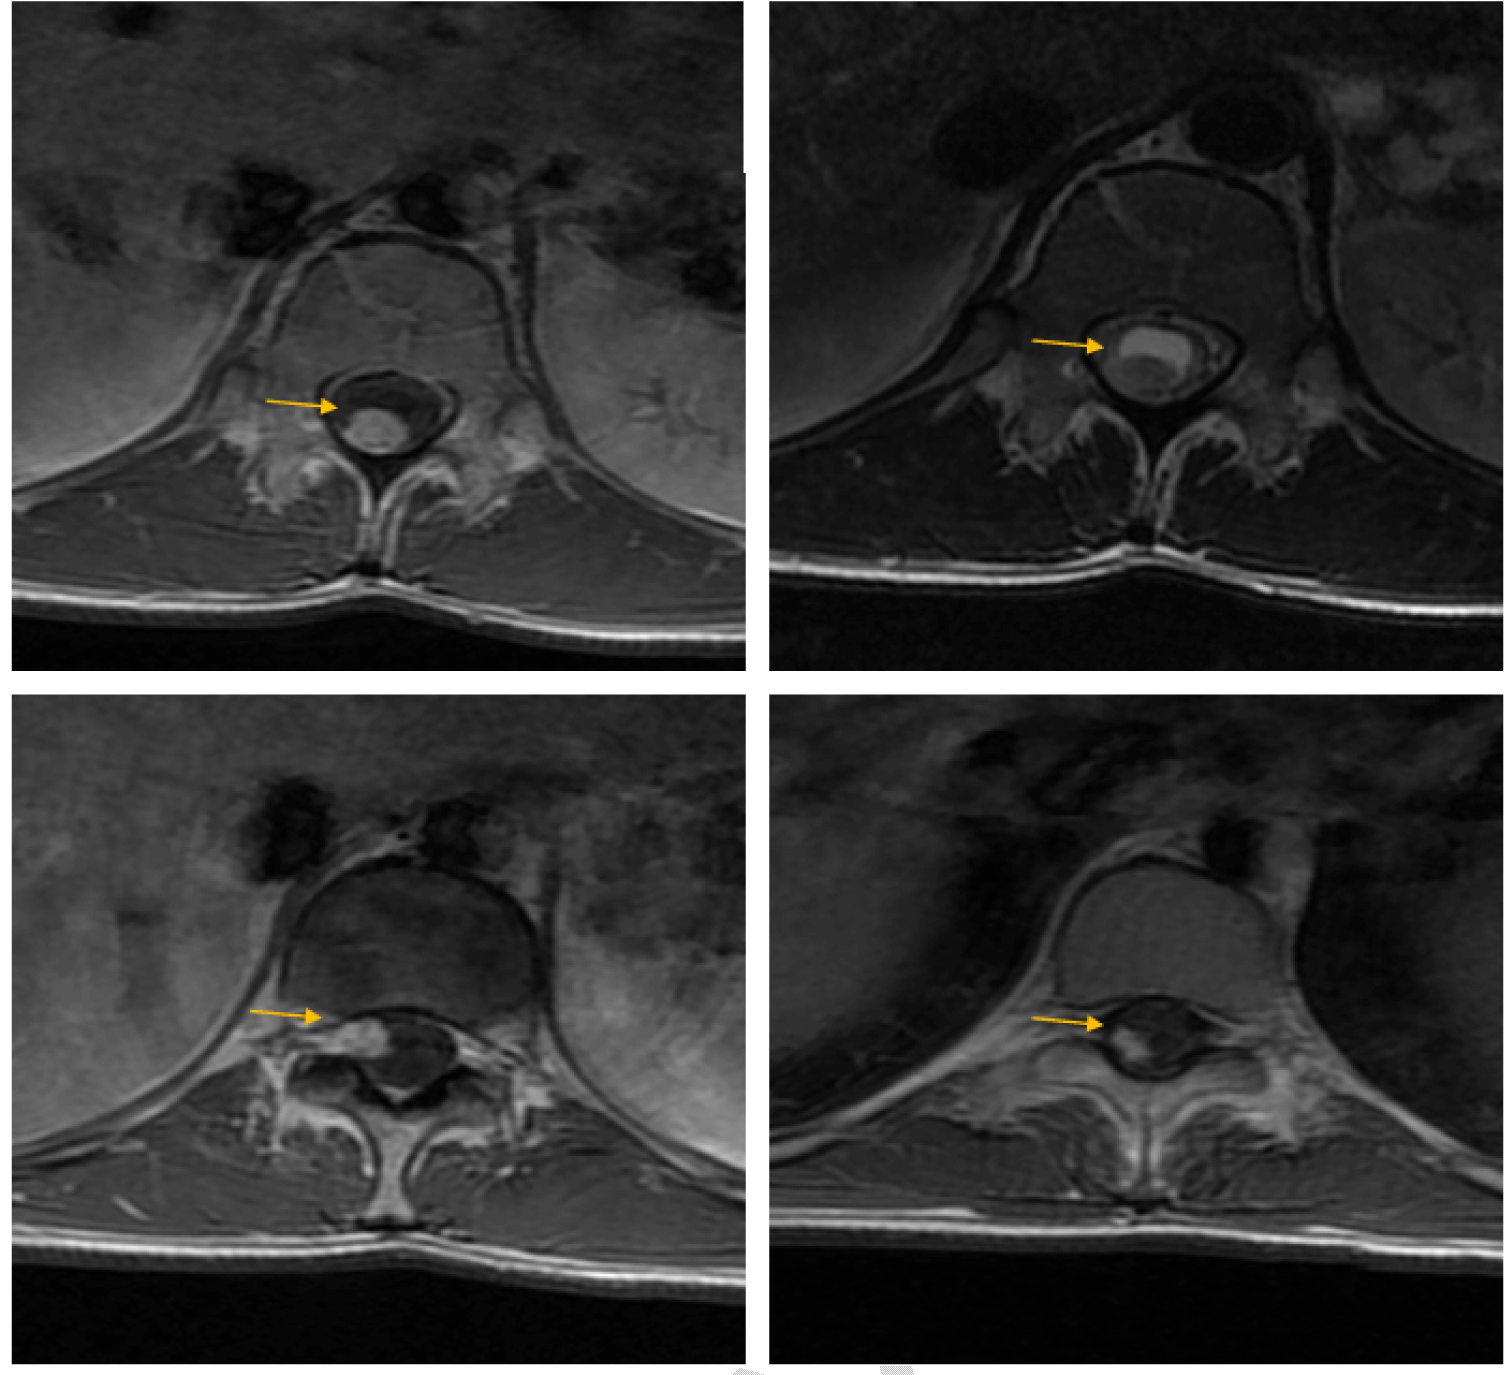

An MRI of the spine showed multiple intramedullary masses. The symptomatic lesions was situated in the terminal cone; the largest mass measured 48×13×1O mm in size. The mass appeared as a cystic lesion with a tissural mural nodule, with hypointense T1 inhomogeneous signal, with increased gadolinium uptake in T1, with perilesional oedema. Just above this mass, there are two other small cystic lesions, up to 1/3 medium of the vertebral body T6; one of the nodules had a subdural extra axial component (Figure 1) and (Figure 2).

Figure 2: Magnetic resonance imaging scan of the spine (axial) showing the three symptomatic intramedullary masses was situated in the terminal cone.

Figure 1: Magnetic resonance imaging scan of the spine showing multiple intramedullary masses. The symptomatic lesions was situated in the terminal cone (red arrow); the largest mass measured 48×13×10 mm in size. The mass appeared as a cystic lesion with a tissural mural nodule, with hypointense T1 inhomogeneous signal, with increased gadolinium uptake in T1.